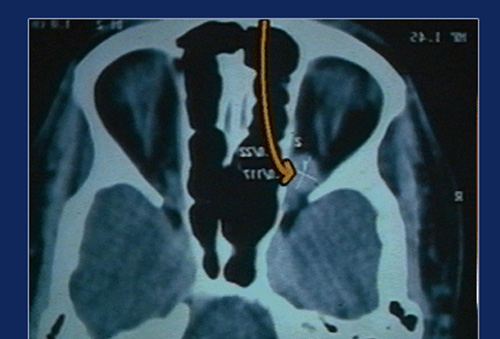

Transnasal Endoscopic approach is employed for removal of tumours and other lesions from the medial and infero medial orbit. The lamina papyracea is a paper thin bone, which can be deliberately opened to expose the orbital contents and extraconal lesions can be removed without much difficulty.

The medial rectus fills almost the entire medial orbit and prevents exposure of the intraconal structures and orbital apex. We have devised a technique of retracting this muscle downwards and posteriorly without compromising its function to obtain good exposure of the Orbital Apex. Well defined, capsulated lesions can be successfully and completely removed using this technique, with little morbidity. We have employed this technique in 30 cases and almost perfected it.

An endoscopic medial orbitotomy and medial retraction techniques were employed to expose the tumour and the same removed in toto